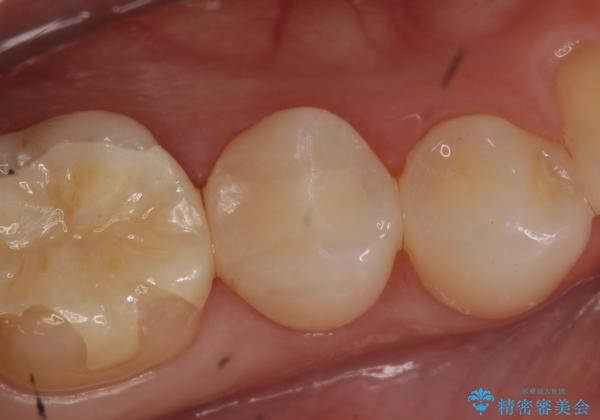

セラミックインレー しみる歯の治療

- 右下5番目の歯がしみるので診て欲しいといらっしゃった方の症例です。

虫歯を除去後、セラミックインレーによる修復を行いました。

当院のセラミックインレーはemaxという強度と審美性に優れた材料を使用しています。

またプレス方式でインレーを製作しているため、削り出しで製作するCADCAMより優れた適合性も持ち合わせており、虫歯が再発しにくい修復物です。